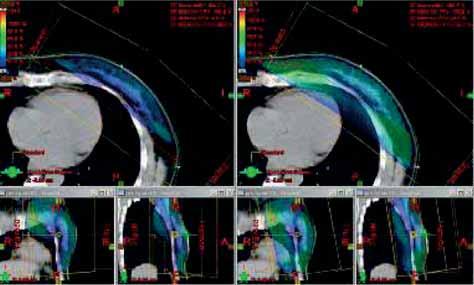

- Při ozařování hrudní stěny s jizvou po totální mastektomii, u

inflamatorního nebo inoperabilní karcinomu je u techniky

tangenciálních polí vhodné použít bolus k dosažení potřebné dávky

na kůži. Bolus na celé pole je doporučován asi na polovinu celkové

ozařovací doby, dále jen na oblast jizvy (Perez C. 1999).

Na ONO Č. Budějovice u pacientek po mastektomii byla měřena dávka TLD na kůži pod bolusem a dávka na bolusu: dávka pod bolusem1,8-2 Gy, na bolusu 1,5-1,6 Gy (obr.5a, b). TLD umožnily zvolit tloušťku bolusu. Na ONO Č. Budějovice se používá bolus na celou plochu tangenciálních polí do 30 Gy, dále je na oblast jizvy a okolí. - Při plánování radioterapie je nutné hodnotit dávku v kritických

Obr. 5 Optimalizace RT tg pole bez bolusu a s bolusem